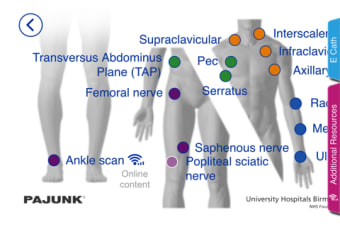

University Hospitals Birmingham NHSFoundationTrustによるiPhone用のフルバージョンプログラム。

Block GuRU Lite strong>は、iPhone用のフルバージョンプログラムであり、カテゴリ「医療」に属します。 a>。

Block GuRU LiteforiPhoneについて

BlockGuRULiteはiOS12.1.2以降で利用できます。アプリの現在のバージョンは5.0.8で、英語でのみ入手できます。 p>